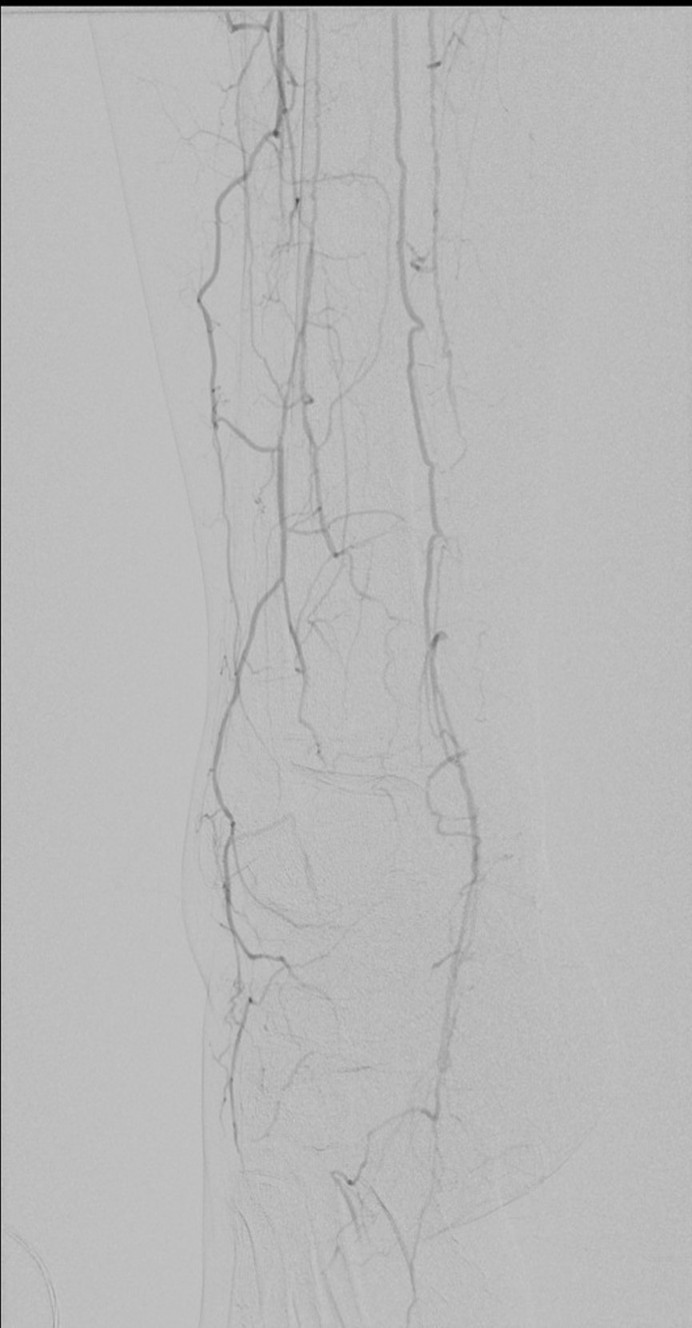

I contacted LeMaitre Vascular and got in touch with your representative, L. Fisher, who promptly sent the Moll Ring Cutters I needed to perform a remote endarterectomy of the patient’s occlusive external iliac and superficial femoral artery plaque. The technical details of remote endarterectomy are have been covered in my blog (https://vascsurg.me/?s=endore), but in the end, through a 7cm incision in the groin (don’t believe the hype, this is minimally invasive), I restored his arteries to their original open condition. Shown below are the results. It was with great sadness that I heard that the LeMaitre Vascular equipment being sent were the last of the stock available in North America. The patient did very well, with the operation completed well before lunch, and is recovering rapidly from his small wound and big rescue. He gets to walk out of the hospital on two legs, but also with the surety that he avoided a major bypass operation, and avoided the short term gains of stenting from the aorta to the profunda -more peel packs and landfill items and a dubious long term durability. Hey, I even used a XenoSure patch on the common femoral.